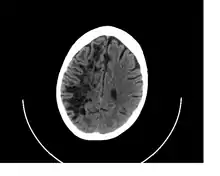

![]() A perivascular space as seen on CT | |